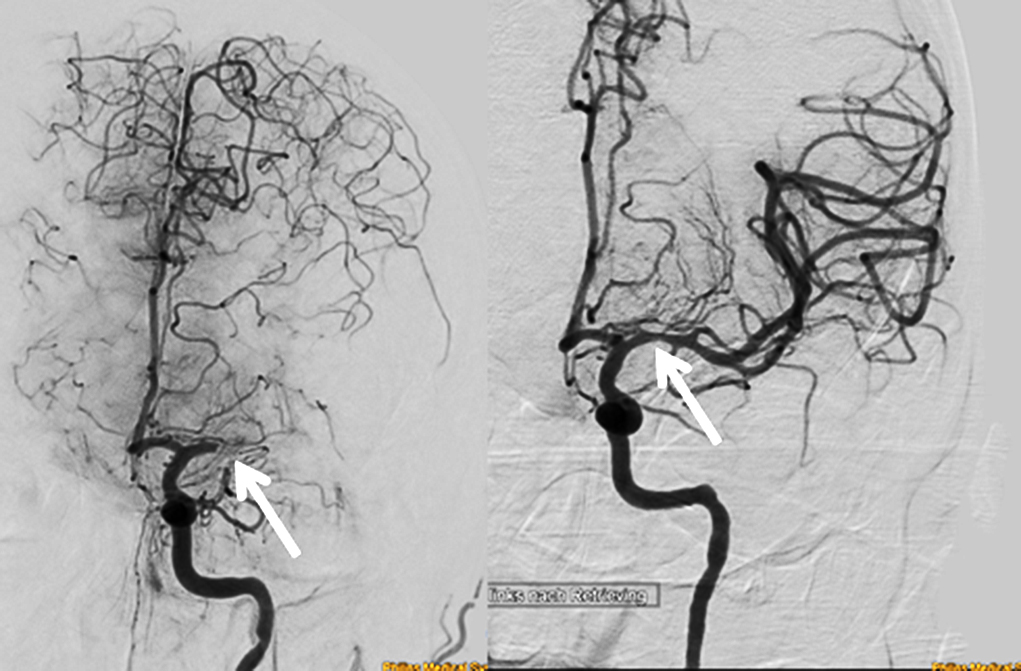

Bei dem als Thrombektomie bezeichneten Verfahren wird ein Katheter in die Leistenarterie eingeführt und bis zum arteriellen Verschluss im Gehirn vorgeschoben. In den Katheter wird ein als Stent bezeichnetes Röhrchen eingebracht, das sich bei Rückzug des Katheters entfaltet und das Blutgerinnsel festklemmt. Anschließend werden Katheter, Stent und mit ihnen das Blutgerinnsel herausgezogen. „Für den Erfolg einer Thrombektomie ist weniger die verstrichene Zeit von Bedeutung, sondern vielmehr, wie die Blutzirkulation im Gehirn aussieht“, sagt Prof. Urbach. Anhand modernster bildgebender Verfahren können erfahrene Ärzte feststellen, wie hoch die Chancen für einen erfolgreichen Eingriff stehen.